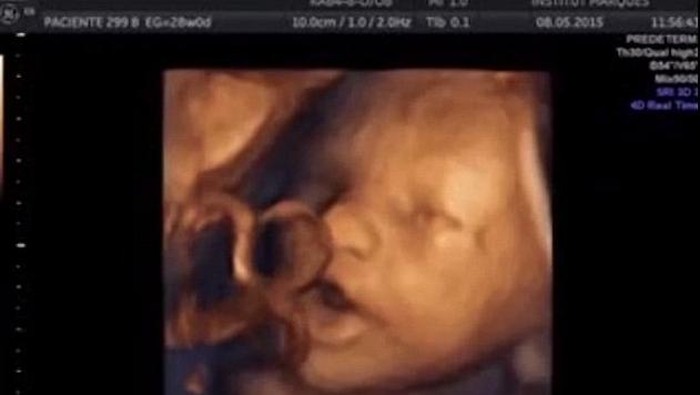

Ada pula janin yang sampai menjulurkan lidahnya (Foto: Institut Marques) |

50 persen lainnya justru melakukan gerakan yang di luar dugaan, yaitu membuka rahangnya lebar-lebar, dan menjulurkan lidahnya sepanjang mungkin. Peneliti semakin yakin bahwa si bayi berupaya merespons suara yang ia dengar, karena gerakan-gerakan itu otomatis berhenti ketika musik juga berhenti diputar.

Ada pula janin yang sampai menjulurkan lidahnya (Foto: Institut Marques)